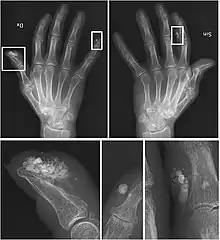

X-rays showing calcinosis in a woman with CREST syndrome

X-ray of subtle calcifications in CREST syndrome

Calcinosis

CREST causes thickening and tightening of the skin with deposition of calcific nodules ("calcinosis").